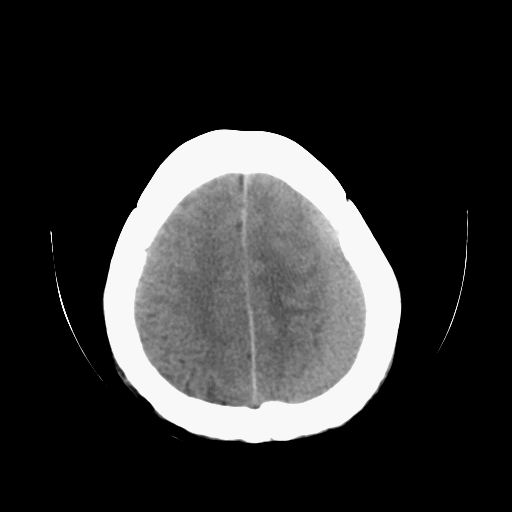

标题: CT13217:头部外伤三月余,头痛三天 [打印本页]

标题: CT13217:头部外伤三月余,头痛三天

左侧慢性硬膜下血肿

太典型,左侧慢性硬膜下血肿

左侧慢性硬膜下血肿,大脑镰下疝。

支持左额颞顶慢性硬膜下血肿伴大脑镰下疝。

血肿是急性、亚急性、还是慢性,要结合外伤时间考虑的,本例头部外伤三个月,应该是明显的慢性硬膜下血肿,但血肿的等密度显然不符合病理改变,估计是合并再次出血,中线结构移位明显,有脑疝形成。应穿刺减压。

血肿是急性、亚急性、还是慢性,要结合外伤时间考虑的,本例头部外伤三个月,应该是明显的慢性硬膜下血肿,但血肿的等密度显然不符合病理改变,估计是合并再次出血,中线结构移位明显,有脑疝形成。应穿刺减压。 大于2个月为慢性出血,2周到二个月为亚急性出血